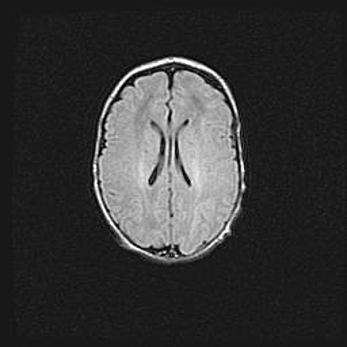

Наружная гидроцефалия с возможной атрофией височных областей.

Возраст: 28 дней

Вес: 3670 г

Пол: мужской

Окружность головы: 38 см

Срок гестации: 40 недель

Гидроцефалия головного мозга у новорожденных – это заболевание, которое характеризуется скоплением избыточного количества спинномозговой жидкости в желудочковой системе головного мозга в результате затруднения её перемещения от места выработки к месту поглощения в кровеносную систему или вследствие нарушения абсорбции. При открытой наружной форме гидроцефалии у новорожденных расширяются и переполняются субарахноидные пространства.

При нормотензивных  формах,  которые,  как  правило,  являются  следствием  перенесенных ишемических  повреждений  паренхимы  мозга,  возможно  сочетание микроцефалии  с нормотензивной гидроцефалией. В основе данных изменений лежит атрофия больших полушарий с преимущественной  локализацией  в  лобно-височных  областях.